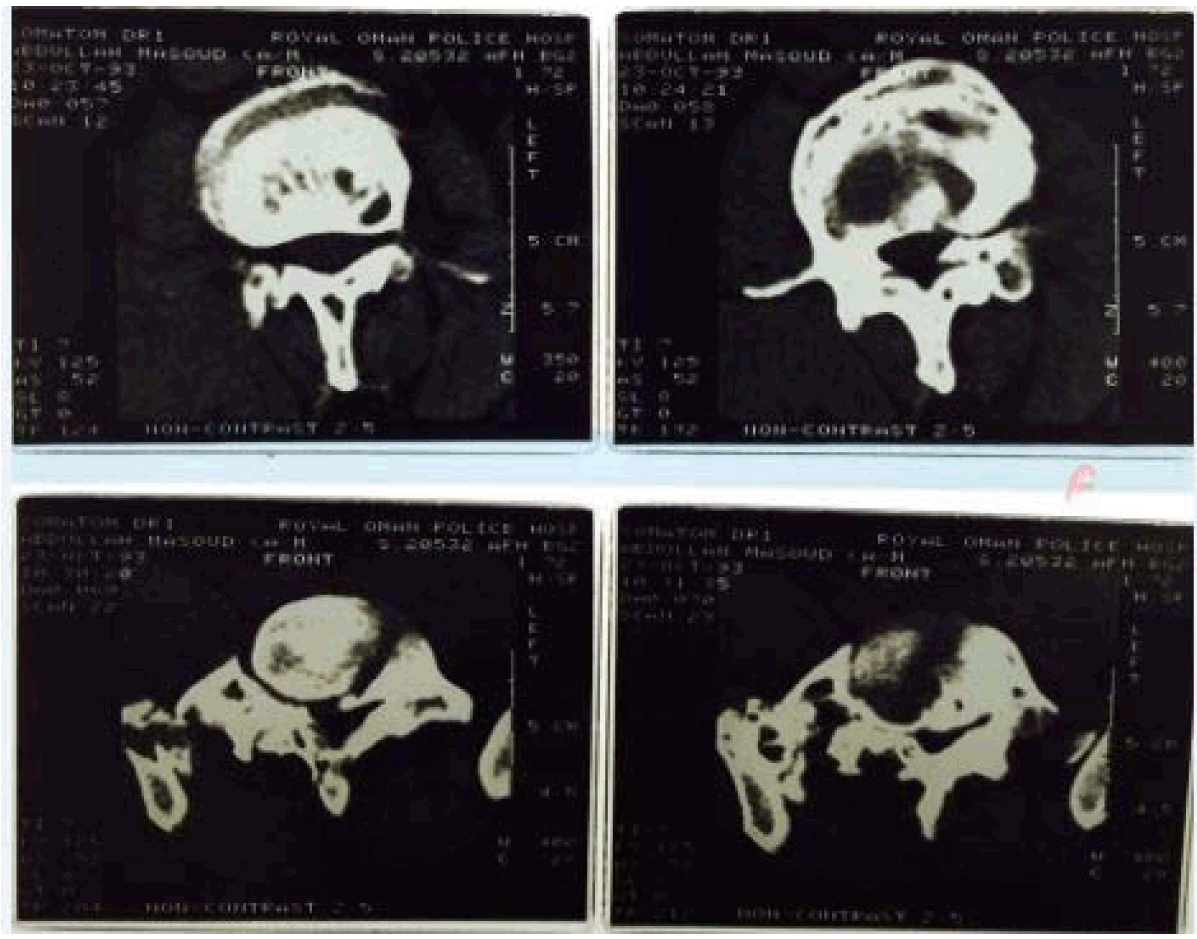

Considering the clinical status and young age of the patient, the radiological findings of multiple vertebral collapse without any history of trauma, effacement of the trabecular pattern with evidence of bony expansion and ground glass attenuation with no significant change in the radiographic findings during three years interval and with no evidence of compressive myelopathy in spite of the advanced spinal changes, a firm clinico-radiological diagnosis of a benign pathology was made with fibrous bysplasia as the possible diagnosis. A nuclear bone scan revealed high uptake of the tracer in the involved vertebrae (Figure 3). Computed tomography (CT) scan of the lumbosacral spine revealed expansile destructive lesions of multiple vertebrae (Figure 4) but these findings did not help in confirming or refuting the diagnosis of fibrous dysplasia.

Figure 4: Computed tomography scan of lumbosacral spine showing expansile destructive lesion of multiple lumbar vertebrae.